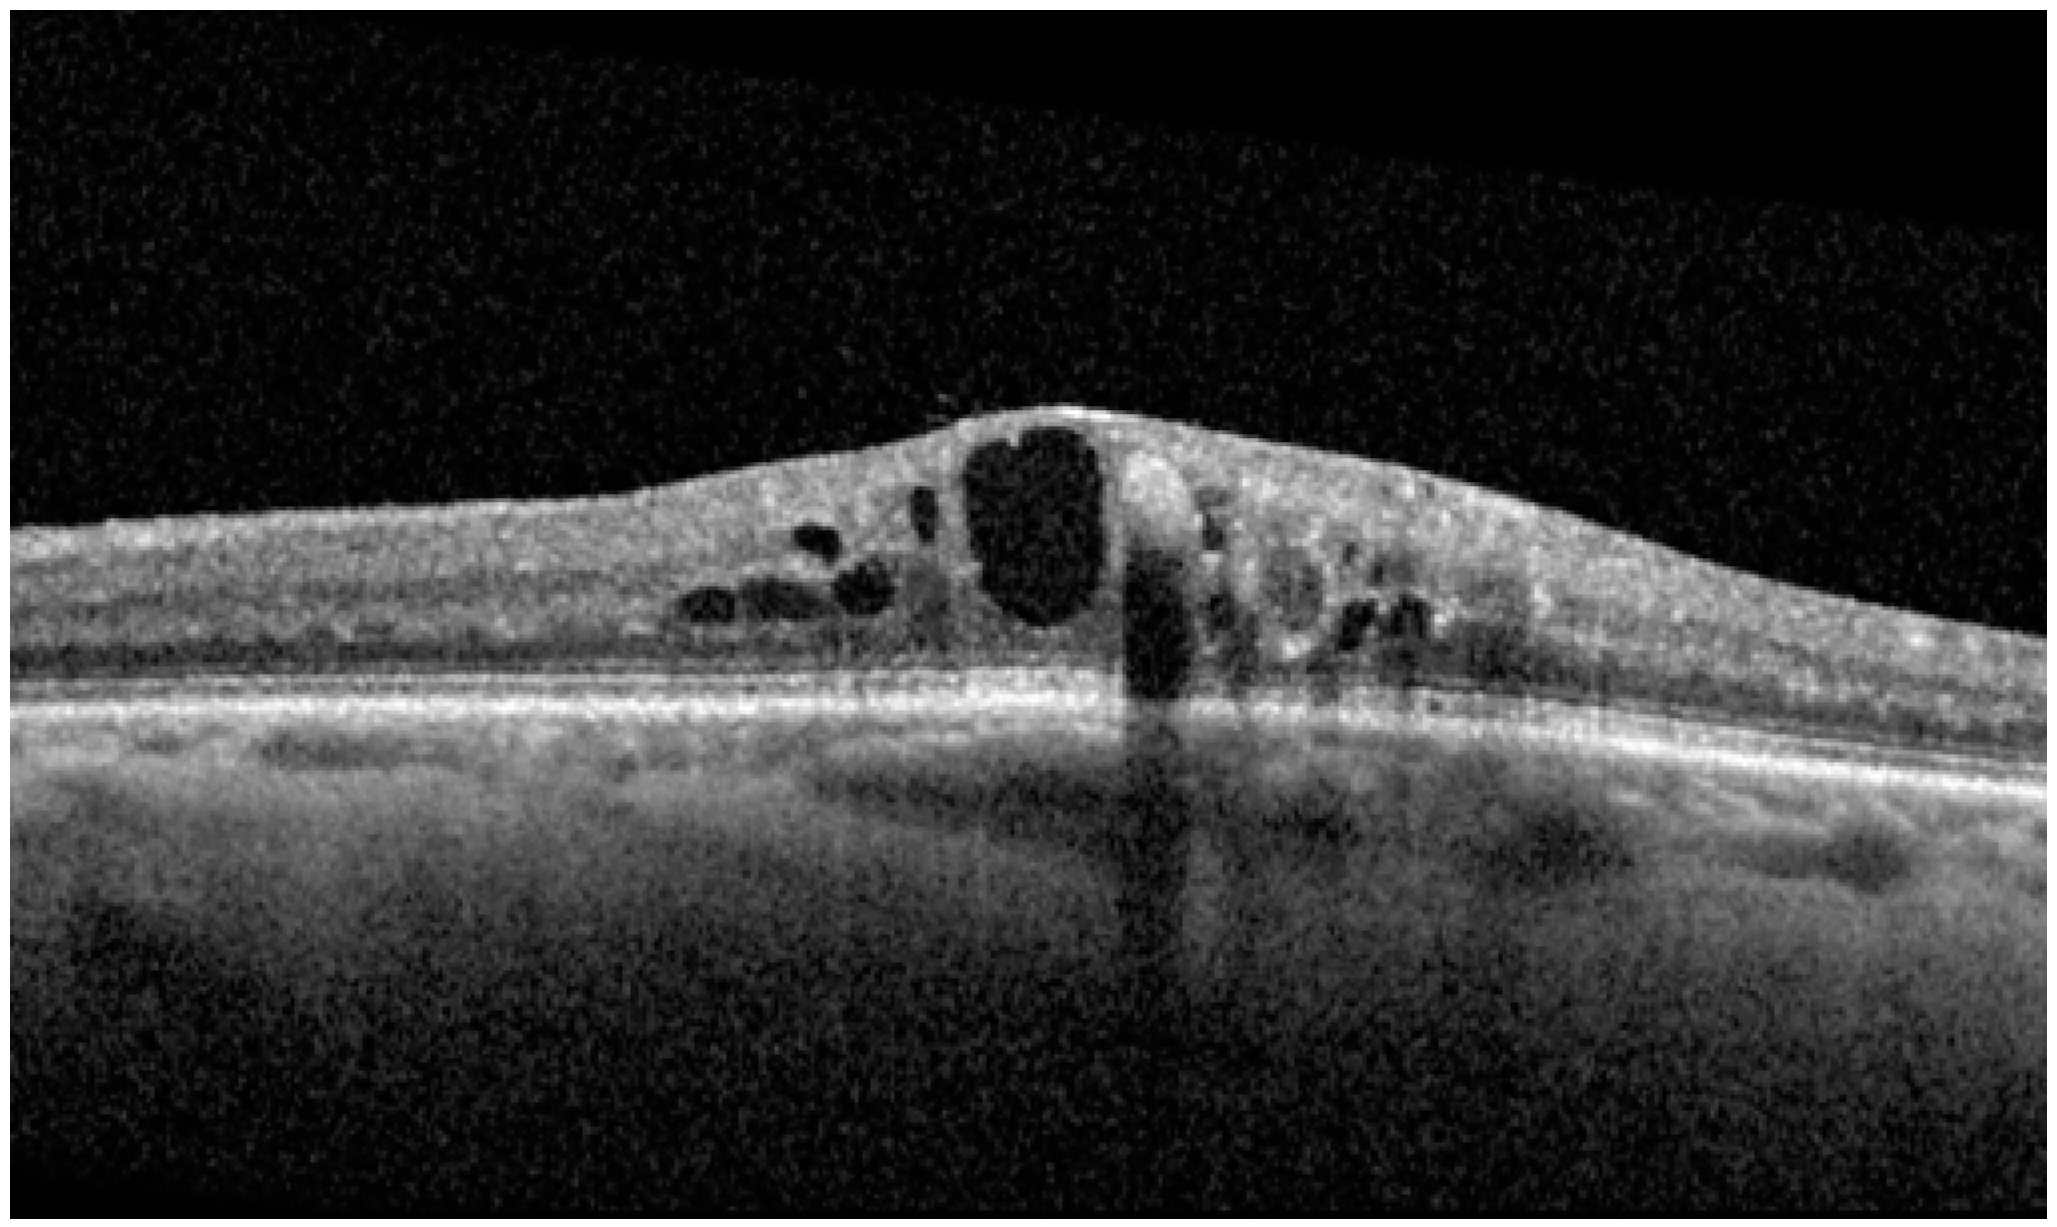

| Central Subfield Thickness, µm (mean ± SD) | 496.93 ± 79.06 | 379.93 ± 116.96 | 0.0001 | 353.53 ± 116.11 | 0.0081 | 334.73 ± 111.99 | 0.0017 | 318.47 ± 99.58 | 0.0073 | 300.67 ± 84.61 | 0.0017 |